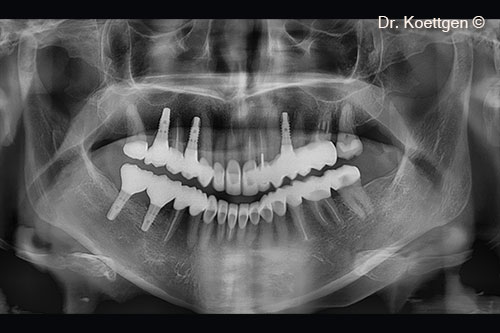

1. OPG - initial

11. OPG - final